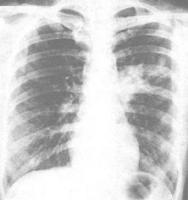

X線檢查?

X線胸片?肺炎呈多樣性,病變範圍不一定與症狀的嚴重度成正比。